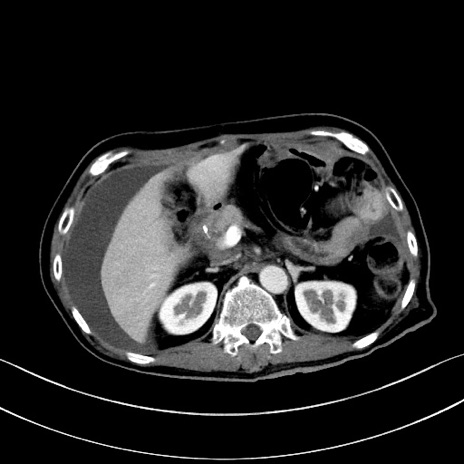

症例28(横断像)

【症例】60歳代男性

【主訴】嘔吐

【現病歴】胃癌にて胃全摘後。食思不振が悪化し、夜中に嘔吐することがある。

【既往歴】胃癌、胃全摘、脾摘、胆摘後

【データ】WBC 5900、CRP 10.56